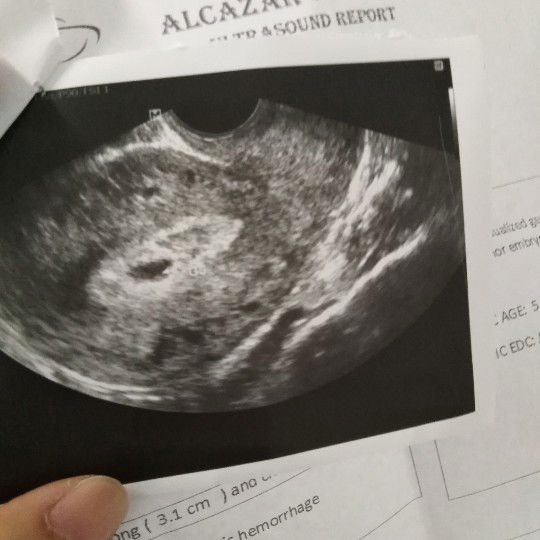

miscarriage

hi ako po yung nagtanong last week tungkol sa spotting, hindi ko pa po tapos yung gamot na nireseta sakin, nagpacheck up ako kahapon and yung result po is hindi na nabuo yung baby 6weeks na sya kahapon?? miscarriage po. kapag ganun po ba ilang months bago po pwede ulit magbaby?

hi mga mommies medyo nagwoworry po ako, last april 14 ung mens ko then this may nag pt ako twice positive kaso nung may 27 nagkaron ako, nagpacheck up ako and transv sabi 5weeks and 3days na daw ako buntis, nirestehan ako ng progesteron utrogestan iinsert sa loob ng pwerta, implantation daw po yung inaakala ko na regla, kaso til now medyo meron pdin patak ng dugo kapag umiihi ako, for 7days nman ung gamot na binigay nya. after 2weeks pa ko babalik kasi wala pang heartbeat na nakita. ok lng kaya yun kahit my dugo pa na lumalabas skin,. nagwoworry ako sa baby eh. ndi nman siguro ko nakunan kasi nung ntransv ako nakita nya my spotting ako.